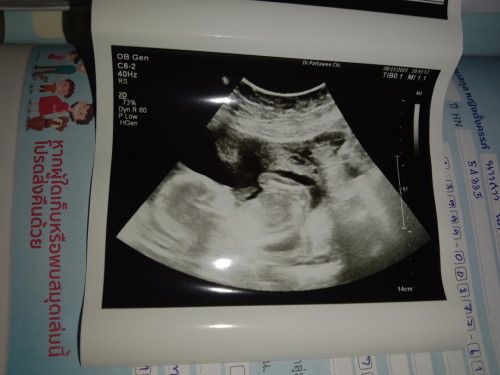

ลุงหมอสูติบอกว่าน่าจะได้ลูกสาวเพราะเห็นไม่ชัดยังไม่ชัวร์

แม่มีโอกาสจะได้ลูกสาวจริงๆไหมค่ะ 18week

อ่านเพิ่มเติมบ้านนี้ซาวตอน16วีค ไม่เห็นเหมือนกันแต่คุณหมอว่าน่าจะผญ เพราะถ้าผช คงเห็นแล้ว🤣 สรุปผลเจาะนิฟออกเลยรุ้เพศ เป็นผญ จริงๆค่ะ